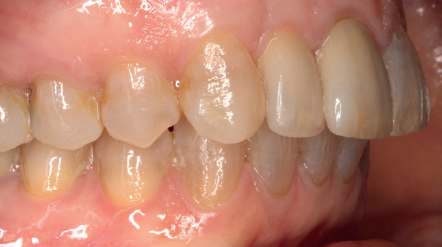

Tres meses después, se comienza con la fase protésica. El estado del tejido gingival es el correcto, aunque a nivel vestibular nos gustaría lograr un descenso del cenit del futuro diente, por lo que se planifica un injerto de conectivo que permita esta conformación de perfil de emergencia más adecuado. El caso se termina con coronas E max a nivel de 1.2 y 1.1, lográndose una sonrisa armónica y completa ente integrada en el resto de la sonrisa, en cuanto a color, emergencia y disposición de los márgenes gingivales (Figuras 14-15). La paciente continua en seguimien o durante años, mantenié dose la estabilidad de la rehabilitación llevada a cabo (Figura 16).